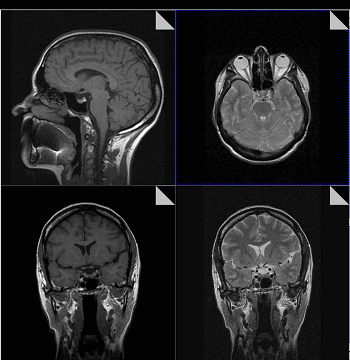

Сосудистые структуры средостения хорошо визуализируются на МР-томограммах ввиду того, что сигнал от просвета сосудов практически отсутствует. Вилочковая железа внутри периваскулярного пространства легче выявляется на МР-томограммах, чем при КТ. Форма, размер, интенсивность сигнала зависит от возраста. У детей вилочковая железа имеет промежуточную интенсивность сигнала, равную интенсивности сигнала от мышц или лимфоузлов. У взрослых интенсивность сигнала от вилочковой железы выше вследствие жировой инволюции, хотя она у разных людей варьирует. Размеры железы у пациентов старше 30 лет, выявленные при МРТ, лучше коррелируют с операционными находками, чем выявленные при КТ. Это связано с лучшей визуализацией инволютивных изменений при МРТ. Хотя вилочковая железа обычно располагается кпереди от крупных сосудов, она может располагаться и ретровазально. Определение локализации вилочковой железы важно для выявления связи аберрантной железы с переднемедиастинальной тимусной тканью но идентификации интенсивности сигнала.

МР-заключение о наличии опухоли вилочковой железы обычно базируется на локальном увеличении железы, выявлении связи опухоли переднего средостения с железой. Интенсивность сигнала от опухоли чаще выше, чем от нормальной ткани железы. Большинство инкапсулированных опухолей дают гомогенный сигнал как на Т1, так и на Т2-изображениях. Инвазивные опухоли чаще негомогенные на Т2-зависимых изображениях.

Хорошая визуализация сосудов при МРТ с синхронизацией позволяет выявлять нечеткость их контуров при инвазии опухолью. Перикард на ЭКГ-синхронизированных изображениях выглядит как тонкая линия, низкой интенсивности толщиной менее 4 мм. При его инвазии возможно выявление прерывистости этой линии с замещением ее высокоинтенсивной опухолевой массой.